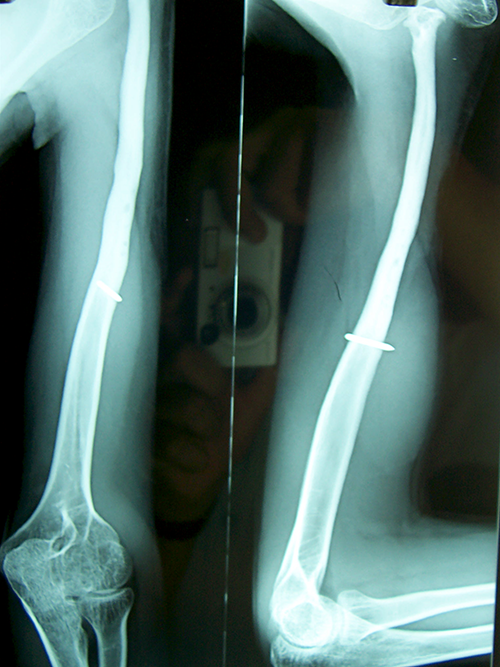

Case:3 Ewings Tibia

Pre-Op

Post-Op